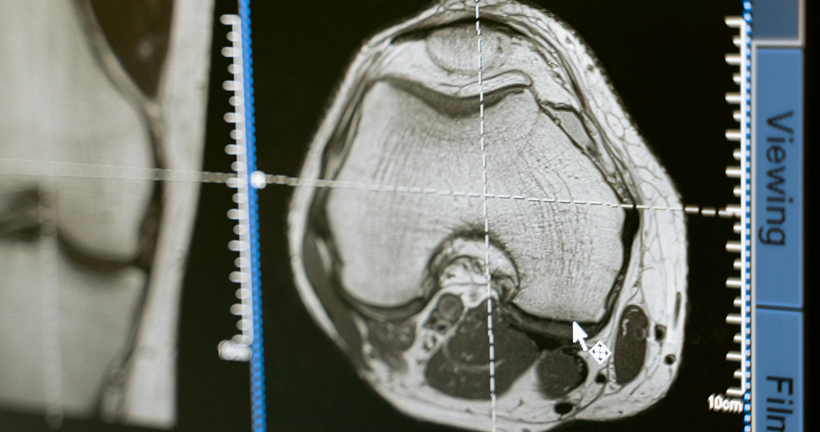

Cristian SantiagoJácome Granda | Investigador La demencia frontotemporal (DFT) es una enfermedad neurodegenerativa compuesta por un conjunto de síntomas comportamentales y del lenguaje como consecuencia de la atrofia de áreas que pertenecen a lóbulo temporal y frontal. Según las características clínicas, la DFT se subdivide en tres variantes. La demencia frontotemporal variante semántica (DFTvnf) que se presenta con alteraciones en el lenguaje, principalmente en la capacidad de comprender y reconocer objetos. La demencia frontotemporal no fluente (DFTvnf) se manifiesta por una marcada disminución en la fluidez, fallo en la emisión de sonidos, así como agramatismo y la demencia frontotemporal variante conductual (DFTvnf) de la cual haremos énfasis en esta investigación, es una enfermedad neurodegenerativa poco estudiada y de inicio insidioso, que se caracteriza por la presencia de síntomas comportamentales y cognitivos que repercuten en el desenvolvimiento adecuado en las distintas actividades de la vida diaria. Dentro de la clínica presentada por pacientes que presente este tipo específico de variante se encuentra disfunción ejecutiva, apatía y desinhibición, además de la disminución en la empatía, alteraciones en los hábitos alimenticios y conductas estereotipadas marcadas, en ocasiones, se manifiesta mediante comportamientos compulsivos y conductas sexuales desinhibidas; los sujetos pueden presentarse agresivos, con una higiene personal desalineada, hiperoralidad, así como coprolalia. A pesar de que este cuadro es el más frecuente, existen perfiles caracterizados por la adinamia y la falta de iniciación. La presentación sintomatológica de la disfunción frontal dependerá de si la afectación predominante inmiscuye a regiones del cíngulo u orbitales. Además, las afectaciones de las funciones ejecutivas dependerán del daño en la corteza dorsolateral. Buscamos describir la relación existente entre la atrofia cerebral identificada en estudios de resonancia magnética estructural, PET-FDG y su implicación cognitiva sobre los pacientes con DFTvnf. La revisión sistemática se realizó bajo los criterios establecidos en la declaración PRISMA, considerando 80 estudios de las bases de datos Pubmed y ScienceDirect en donde por criterios de inclusión y exclusión la revisión final se realizó con 40 artículos de las bases de datos antes descritas. Como resultados en relación con los estudios analizados, se encontró que solo el 15% de artículos mantienen una correlación de áreas anatómicas - cognitivas, además se encontraron alteraciones en los dominios de atención, memoria y funciones ejecutivas mientras que los hallazgos de atrofia cerebral se localizan en áreas frontales, el cíngulo e ínsula. El diagnóstico de la DFTvnf es un proceso complejo que se compone de distintas etapas, por lo que, la presente revisión sistemática confirma la importancia de estudio de las manifestaciones clínicas, la evaluación neuropsicológica de procesos cognitivos y el papel de las técnicas de neuroimagen en la identificación de este tipo de variantes. Estos resultados contribuirán a obtener un diagnóstico oportuno y veraz de la DFTvnf, describir las manifestaciones clínicas de manera más específica además de beneficiar a los profesionales del área para la implementación de intervenciones adecuadas que permitan mejorar la calidad de vida de quienes la padecen. Leer el artículo completo

DR. CRISTIAN E. LEYTON Y DR. RAMÓN LANDIN-ROMERO | FACULTY OF HEALTH SCIENCES, THE UNIVERSITY OF SYDNEY. SYDNEY, AUSTRALIA. En los últimos años el interés científico en las enfermedades neurodegenerativas ha crecido considerablemente. Esto ha sido motivado por el gran incremento en el número de personas afectadas por estas dolencias, unido al advenimiento de nuevas técnicas y métodos de evaluación que han posibilitado un mejor conocimiento sobre las mismas. En los últimos 10 años, grupos internacionales de investigadores han actualizado los criterios diagnósticos de demencia, incorporando el uso de imágenes cerebrales y otros marcadores biológicos en la valoración del juicio clínico. Las demencias frontotemporales son un conjunto amplio y heterogéneo de enfermedades neurodegenerativas que afectan frecuentemente a pacientes menores de 65 años. Se manifiestan a nivel clínico con cambios graduales en la personalidad y en el lenguaje, a diferencia de la enfermedad de Alzheimer que se asocia a una pérdida gradual de la memoria. Las demencias frontotemporales también se asocian con la acumulación tóxica de al menos dos proteínas distintas en las neuronas, mientras que la enfermedad de Alzheimer se caracteriza exclusivamente por la acumulación de ovillos neurofibrilares y placas de amiloideas en el cerebro. De acuerdo con la prominencia de las manifestaciones clínicas, las demencias frontotemporales pueden clasificarse en dos grandes grupos; la variante conductual y la variante afásica, esta última también referida como afasia progresiva primaria. La variante conductual cursa con cambios larvados de la personalidad y comportamiento. Estos síntomas son a veces difíciles de determinar y cuantificar, debido a que su valoración clínica depende del relato del cónyuge, familiares, amigos o colegas del paciente. Frecuentemente los familiares relatan conductas sociales inapropiadas, pérdida del decoro y cortesía, como también falta de empatía y contacto social, y pérdida de interés en pasatiempos. En muchos casos, las alteraciones conductuales dan lugar a conflictos conyugales, problemas interpersonales o dificultades laborales que pueden camuflar los síntomas primarios de la enfermedad y retrasar el diagnóstico. Debido a que este tipo de demencia afecta mayoritariamente a personas menores de 65 años, los síntomas también se pueden confundir con crisis existenciales, episodios depresivos, trastorno bipolar u otras alteraciones psiquiátricas propias de esta edad. La evaluación de las funciones mentales superiores, de gran relevancia en la demencia frontotemporal, se efectúa mediante una evaluación neuropsicológica. Ésta puede evidenciar deterioros en la capacidad para ejecutar actividades complejas que requieren habilidad de planificación, jerarquización y resolución de conflictos. No obstante, la evaluación de estas habilidades (también conocidas como funciones ejecutivas) presenta ciertas limitaciones, ya que muchos pacientes con demencia frontotemporal muestran un rendimiento limítrofe o dentro del rango normal en comparación con personas sanas de la misma edad. Nuevas técnicas como la resonancia magnética nuclear, permiten visualizar la anatomía del cerebro con gran detalle en pacientes con demencia en vida. El estudio de resonancia cerebral es además fundamental para descartar otras posibles causas de demencia, como la presencia de tumores o de enfermedad cerebrovascular. Las imágenes de resonancia en pacientes con demencia frontotemporal detectan una reducción significativa del tamaño de la parte delantera del cerebro, que incluye la parte inferior de los lóbulos frontales y la parte anterior de los lóbulos temporales. Sin embargo, en estadios temprano de la enfermedad, los cambios cerebrales son sutiles y muchas veces el clínico debe observar la progresión de los síntomas para establecer un diagnóstico certero. La ausencia de síntomas clínicos claramente definidos ha motivado que los criterios diagnósticos actuales estratifiquen el grado de certeza diagnóstico en tres niveles; definitivo, posible y probable. El diagnóstico definitivo se establece cuando el examen histológico revela cambios patológicos en el cerebro y/o cuando existe en el paciente una mutación genética causante de la enfermedad. El diagnóstico posible se establece ante la presencia progresiva de los cambios conductuales y/o fallos en pruebas neuropsicológicas. Por último, el diagnóstico probable requiere además la presencia de cambios en las imágenes cerebrales y un deterioro funcional significativo en las actividades de la vida diaria. En el otro espectro clínico de la demencias frontotemporales están las afasias primarias progresivas. En contraste con la variante conductual, las afasias progresivas presentan un deterioro progresivo del lenguaje que es bastante evidente para el paciente y familiares. Característicamente, las alteraciones del lenguaje son relativamente aisladas y respetan otros dominios cognitivos, al menos durante las fases iniciales de la enfermedad. La presentación afásica, sin embargo, exhibe un amplio rango de alteraciones del lenguaje que afectan la capacidad para comprender o producir palabras u oraciones adecuadamente. Los criterios actuales definen tres variantes clínicas; semántica, no-fluente/agramática y logopénica, cada una de las cuales presentan un patrón único de alteración lingüística, distribución de atrofia cerebral y patología asociada. La variante más enigmática es la variante semántica o también conocida como la demencia semántica. La alteración lingüística cardinal es la pérdida del significado de las palabras y una reducción del vocabulario, que es reflejo de una disolución del conocimiento conceptual sobre el mundo. La demencia semántica se asocia a una desintegración de la información enciclopédica que se acumula a largo de la vida que causa dificultades no sólo para reconocer objetos y palabras, sino que también para identificar a las personas, sonidos y canciones. Las personas con demencia semántica pueden pasar desapercibidas, ya que presentan un lenguaje fluido, se incorporan con facilidad a una conversación y realizan actividades cotidianas de forma normal, al menos al inicio de la enfermedad. Las imágenes cerebrales muestran de manera consistente una reducción del tamaño de la parte anterior de los lóbulos temporales y la patología microscópica muestra la acumulación anormal de una proteína llamada ‘TDP-43’. La variante no-fluente/agramática, como su nombre lo indica, se caracterizada por dificultades para articular palabras, y construir y comprender oraciones. Sin embargo, al contrario de la variante semántica, la comprensión del vocabulario está preservado. Las imágenes cerebrales muestran una reducción de la masa cerebral de la parte inferior del lóbulo frontal izquierdo (área de Broca), un área que tiene un rol establecido en el habla y procesamiento morfosintáctico. La patología microscópica muestra acumulación anormal de una proteína llamada ‘tau’. Finalmente, la variante menos conocida, pero no menos importante, es la afasia logopénica, cuyo vocablo es derivado del griego y literalmente significa “escasez de palabras”. Como su nombre lo indica, las personas con la afasia logopénica presentan dificultades para encontrar palabras, lo que genera constante interrupciones y circunlocuciones. En contraste con otras variantes, no hay distorsiones en el habla y el conocimiento de las palabras está preservado. Sin embargo, estos pacientes muestran dificultades para evocar las palabras a pesar de conocerlas. En algunos casos, la construcción de las palabras es defectuosa debido a la transposición, reemplazo o desplazamiento de sílabas, que se hace más evidente con palabras más largas. La repetición de oraciones está consistentemente alterada, no solamente debido a los errores silábicos mencionados, sino que también por la incapacidad de retener todos los componentes de la oración en la memoria de corto plazo. Las imágenes cerebrales demuestran atrofia de la parte lateral del hemisferio izquierdo, en la unión entre el lóbulo temporal y lóbulo parietal. De forma importante, y en contraste con otras variantes de demencia frontotemporal, la mayoría de los casos de afasia logopénica, se asocian a con cambios microscópicos propios de la enfermedad de Alzheimer. Este hecho es de gran relevancia, ya que demuestra que la enfermedad de Alzheimer puede presentarse sin alteraciones en la memoria, pero con importantes problemas en la producción del lenguaje. En tan solo una década, el mundo de la investigación en demencias ha experimentado un notable desarrollo. Sin embargo, nuevos paradigmas son necesarios para comprender cómo la acumulación de las ciertas proteínas promueve distintos patrones de atrofia cerebral que a su vez dan lugar a la emergencia de diversos síndromes clínicos. Uno de los grandes desafíos de la neurociencia actual es, no solamente la detención del desastroso avance de estas enfermedades, sino además la determinación precoz de los síntomas. La identificación de mecanismos genéticos asociados al riesgo de desarrollar demencia a lo largo de la vida, servirá para implementar a tiempo intervenciones que puedan modificar, o mejor aún, detener la progresión de la neurodegeneración antes de la aparición de los primeros síntomas.